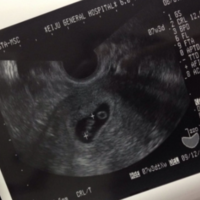

正常来说,孕囊会随着孕期的推进而一天天长大,孕妇也能从每次的B超检查图像中看到孕囊一天天变大。但并不是所有孕囊都会长大,有些孕囊十天不长,而胎心胎芽是存在的,这种情况在临床上也常见,也不算胎停,也有可能是胚胎发育慢导致的,比如说孕妇的孕酮不高或营养不良等。一般来说,在还有胎心胎芽的情况下,即使孕囊不长或者长得比较慢,保住的可能性比较大。这种情况最好是到医院去给医生检查评估。孕囊10天不长但胎心胎芽...

浏览量98 发表于 2023-06-29